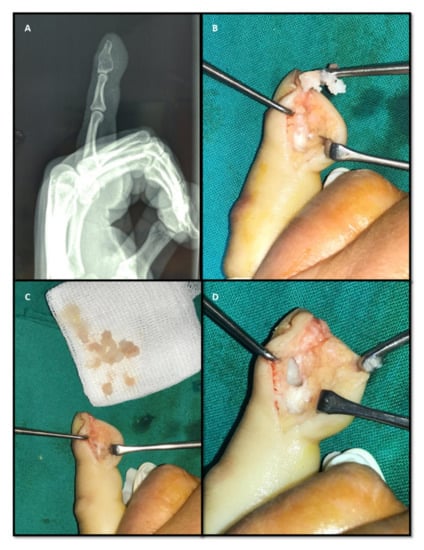

In the cases in which an injectable bone substituent was used, a thin radiolucent line was observed between the substituent and the recipient’s bone. Subsequent postoperative X-rays revealed a reduced radiolucency of this line due to the development of new bone tissue in the k-IBS® substituent, a process favored by its osteoconductive properties. The ceramic granules in k-IBS® composition are rapidly osteointegrated due to their chemical composition similar to human bone. On 1-year follow-up X-rays, a complete replacement of the substituent by spongy bone tissue was observed in all cases (Figure 3).

Figure 3. Complete integration of the k-IBS® injectable bone substitute at 12 months.